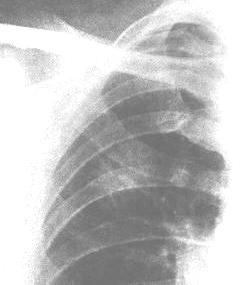

1.X 線檢查 氣管的後前位及側位體層像、氣管分叉體層像對診斷氣管、支氣管腫瘤有重要意義。這些檢查可清晰地顯示氣管腔內腫瘤的輪廓、位置、範圍和病變與鄰近器官的關係。良性腫瘤可有鈣化,基底有細蒂。惡性腫瘤基底寬,邊界、輪廓均不完整。行後前位氣管體層像時,囑病人說“E”,可以很好地顯示後前方向的喉部以及氣管全長的詳情;照側位氣管像時做吞咽動作,能使喉部抬高,從而清晰地顯示喉與氣管的關係;左、右後斜位氣管體層像對顯示器官,尤其是支氣管各主要分支的病變有很大幫助。

2.CT 檢查 對氣管腫瘤的診斷有很大幫助。CT 可顯示氣管腔內的密度增高的軟組織影,多為偏心性,氣管壁增厚,氣管呈不規則狹窄,大約10%的氣管腫瘤沿氣管周圍生長,30%~40%的氣管腫瘤直接累及縱隔。支氣管腫瘤在CT 上可表現為向腔內生長或向腔外浸潤,引起支氣管不全或完全梗阻,出現阻塞性肺炎或肺不張,根據支氣管腫瘤的浸潤程度,Naidich 等將其分為6 種表現:①支氣管壁顯示正常;②支氣管壁均勻狹窄;③支氣管不規則狹窄;④支氣管腔完全阻塞;⑤支氣管腔內腫塊;⑥支氣管受壓移位。